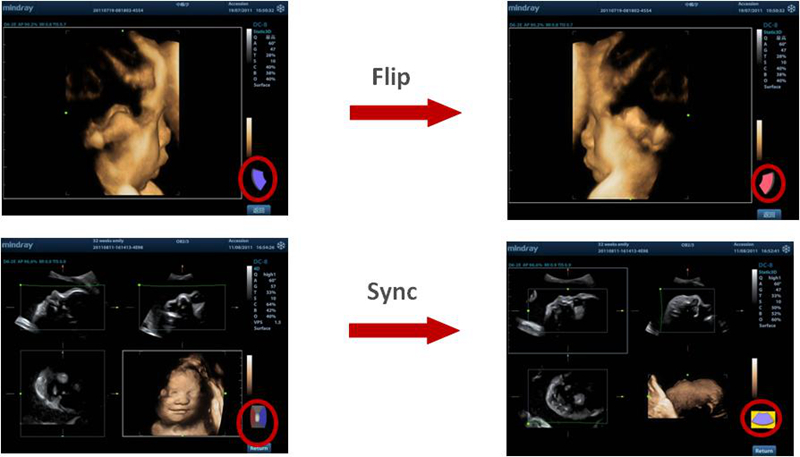

Adquisición de imagen 3D/4D

Funciones de rotación y sincronización 3D/4D, lo que ofrece una visualización de la imagen en volumen de forma sencilla y rápida desde cualquier dirección.

20161102112120_3065